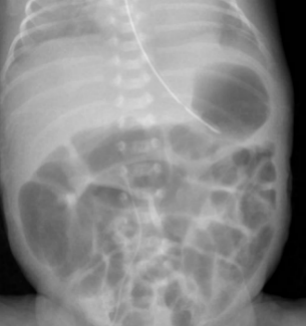

临床病例:患儿日龄1个月12天,女,孕1产1,在孕26周时因“胎盘早剥”剖宫产娩出,无胎膜早破,血性羊水,出生体重660g,双胎之先娩出者,生后Apgar评分1分钟为8分,5分钟、10分钟均为9分,以“超早产儿、超低出生体重儿、新生儿呼吸窘迫综合症、双胎儿”转入我科进一步治疗。患儿入院后予早产儿配方奶喂养。患儿奶量增加缓慢。表现为腹胀、肠鸣音弱、奶量增加困难、偶有吐奶、排粘液便。无肉眼血便。化验检测显示嗜酸性粒细胞增高,波动在20-25%之间。间断监测腹片显示肠管僵直、肠管充气不均匀(如下图所示)。未见肠壁积气和门静脉积气。患儿有过敏性疾病家族史。予更换为深度水解奶后患儿腹胀较前缓解,肠管充气均匀,无明显扩张。奶量增加顺利。嗜酸性粒细胞下降至5-8%。

更好奶粉后